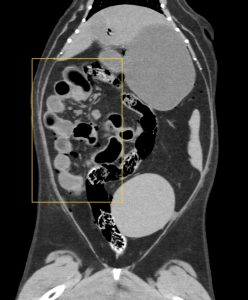

CT検査でも同様の所見があり、胃の出口(青丸)から大腸まで手繰られていました。(オレンジ四角)